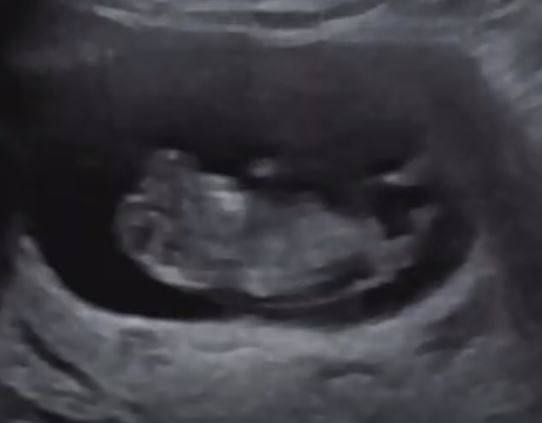

양수 터지기 바로 전날 정기검진 날이어서 둘째 초음파를 보고 왔습니다. 처음 검진 때는 아기가 콩의 형태여서 전혀 인간스럽지 않았으나 전날 검진의 아기는 이미 작은 사람이었습니다. 팔, 다리, 머리를 다 보여주고 4cm나 자란 상태였습니다.

바로 전날 이미 사람 형태의 초음파를 봐버린 나는 4cm나 커버린 아기를 지금 바로 마주할 자신이 없었습니다. 달리는 차 안에서 제발 아기가 살게 해달라고 빌었습니다. 하지만 이미 많은 양의 양수를 쏟았기 때문에 마음의 준비를 해야 할 것 같았습니다. 정신없이 병원에 도착해서 긴급으로 진료를 받고 바로 휠체어에 탄 채 입원했습니다.